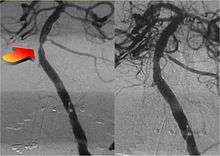

- Cerebral aneurysm

- Extracranial (brachiocephalic) atherosclerosis

- Intracranial atherosclerosis

- Stroke